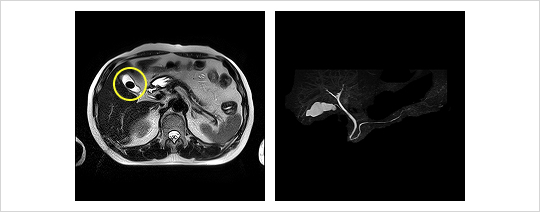

MRCP(磁気共鳴胆道膵管造影)

狭い所で20分ほどじっとしなくてはなりませんが、造影剤を使わなくても鮮明な画像が得られます。DICで分かりにくい時などは追加で検査します。